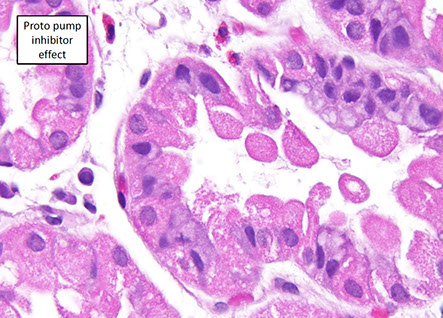

Proton pump inhibitor effects

Reduced acid secretion in gastric parietal cells; changes can also be seen in pts not taking PPIs

- micro: parietal cells are hyperplastic c granular / vacuolated cytoplasm c apical snouts

PPI effects [1]

Histology slide of the antral-type gastric mucosa with slight atrophy (A), characterized by a reduction in the number of gland bodies in PPI user. (B) Fundic glands of a proton-pump user. A polyp of the fundic glands can be observed in panoramic view, highlighting the dilation of the crypts. (C) Magnification of the fundic gland polyp, showing the dilated crypt covered by fundic-type mucosa. (D) Numerous spiraled bacteria (black) are present on the surface of the epithelium and in the interior of the crypt in PPI user. (A and C - Hematoxylin-eosin, 400×; B - Hematoxylin-eosin, 100×, D - Wartin-Starry, 400×).